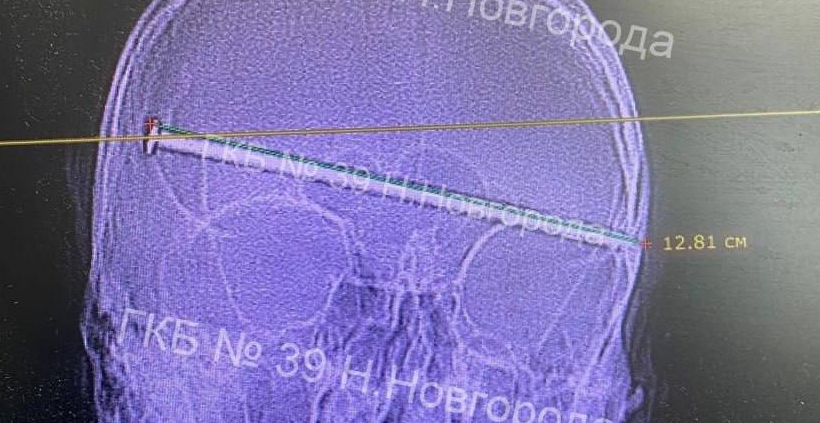

Железный штырь вошел в череп пациента полностью, вместе со шляпкой, ему не хватило буквально пару миллиметров, чтобы мозг насквозь.

Жизнь и здоровье мужчине спасли нейрохирурги из больницы №39. Операция по извлечению гвоздя длилась более трех часов. Следующие сорок дней после пациент провел в коме, но в итоге пришел в себя и уже проходит реабилитацию.